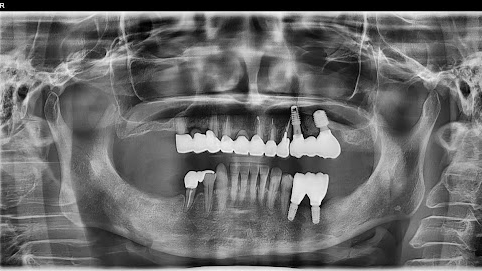

Before

枚方市のインプラントの症例

After

M・I 様 女性 70代

症状としては、左下56は、歯周病で欠損したと考えられるが、かなりの骨欠損をともなっていた。左上456に関しては、動揺が大きく、炎症が起き、排膿、および、歯性上顎洞炎を起こしていた。

治療法としては、動揺がひどくなってきて、炎症の症状もあったため、左上56の抜歯を希望。インプラント治療をその後、希望したため、左上4に関しては抜歯即時埋入。左上6に関しては、既存骨1から2mmでインプラント治療が厳しい状態であったが、グラフトレスサイナスリフトを行い、治療期間5か月はかかるということを説明して、インプラント埋入をおこないました。その後、2か月半後、大幅に骨が欠損している下顎56に対して、ショートインプラントを使用して、下顎神経の損傷を避けて、インプラント埋入を終えています。その後2か月後に光学印象で印象を行い、上顎刺億456歯、3ユニットのジルコニアブリッジを装着。下顎左側56に関しては、骨欠損が大きいため、歯冠長がだいぶ長くなるため、ジルコニアの連結冠を装着して治療を終えた。

治療結果は、上顎6に関しては、既存骨が少なく、厳しい治療ではありましたが、5か月で治療を終え、患者様の負担を最小限に抑えるができたと考えます。(従来のサイナスリフトでは、このようなケースでは1年以上、1年程度の治療期間がかかるか、治療が不可能と言われるケースだと考えます。)また、下顎は骨欠損が大きく、下歯槽管のリスクが起きることが考えられますが、ショートインプラントを使用することで安全に治療を行うことができました。

治療の期間・回数:治療期間5か月(上顎456 3ピースブリッジの治療は5か月(上顎既存骨が2mm程度しかなく、骨結合に時間がかかるケースであったために、5か月の治療期間が必要であった。)(左下56に関しては2か月半で治療を終えています。)治療回数は、13回。

治療の価格:1,474,000円(税込)

治療費の内訳:左上46および左下56のインプラント基本料(フィックスチャー及び手術費用、投薬費用、レントゲン費用、インプラント上部費用(アバットメントおよびジルコニアクラウンの費用用)330000円(税込み)×4本分 1320000円(税込)。左上5ジルコニアポンテック費用88000円(税込)。オプション費用、左上4抜歯即時埋入加算(人工骨費用を含む)+グラフトレスサイナスリフト費用 33000円(税込)、左上6グラフトレスサイナスリフト費用 33000円(税込)

治療のリスクや副作用:手術後に、痛みや腫れ、出血、合併症などを引き起こす可能性があります。噛む感覚がご自身の歯と異なる場合があります。見た目がご自身の歯と異なる場合があります。手術後にメインテナンスを継続しないと、インプラントが抜け落ちる可能性があります。